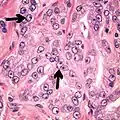

Adenocarcinoma with two mitoses in reactive epithelium.

Acinar adenocarcinoma with intraluminal blue mucin.

- Mitoses (also seen in for example high-grade prostatic intraepithelial neoplasia (HGPIN) and prostate inflammation).[4]

- Prominent nucleoli[4]

- Intraluminal eosinophilic secretion[4]

- Intraluminal blue mucin[4]